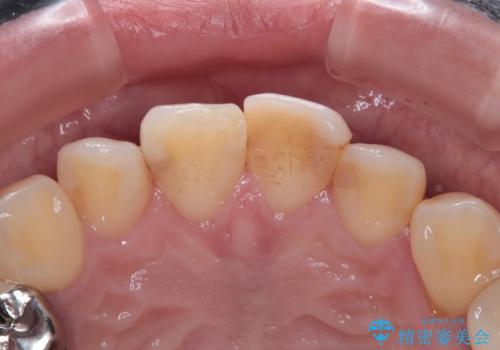

- 以前保険診療で行った前歯を自然できれいなセラミックにしたいと来院された患者様です。

古い材料と虫歯を除去して、土台の形を整え、より自然なオールセラミッククラウンにすることとしました。